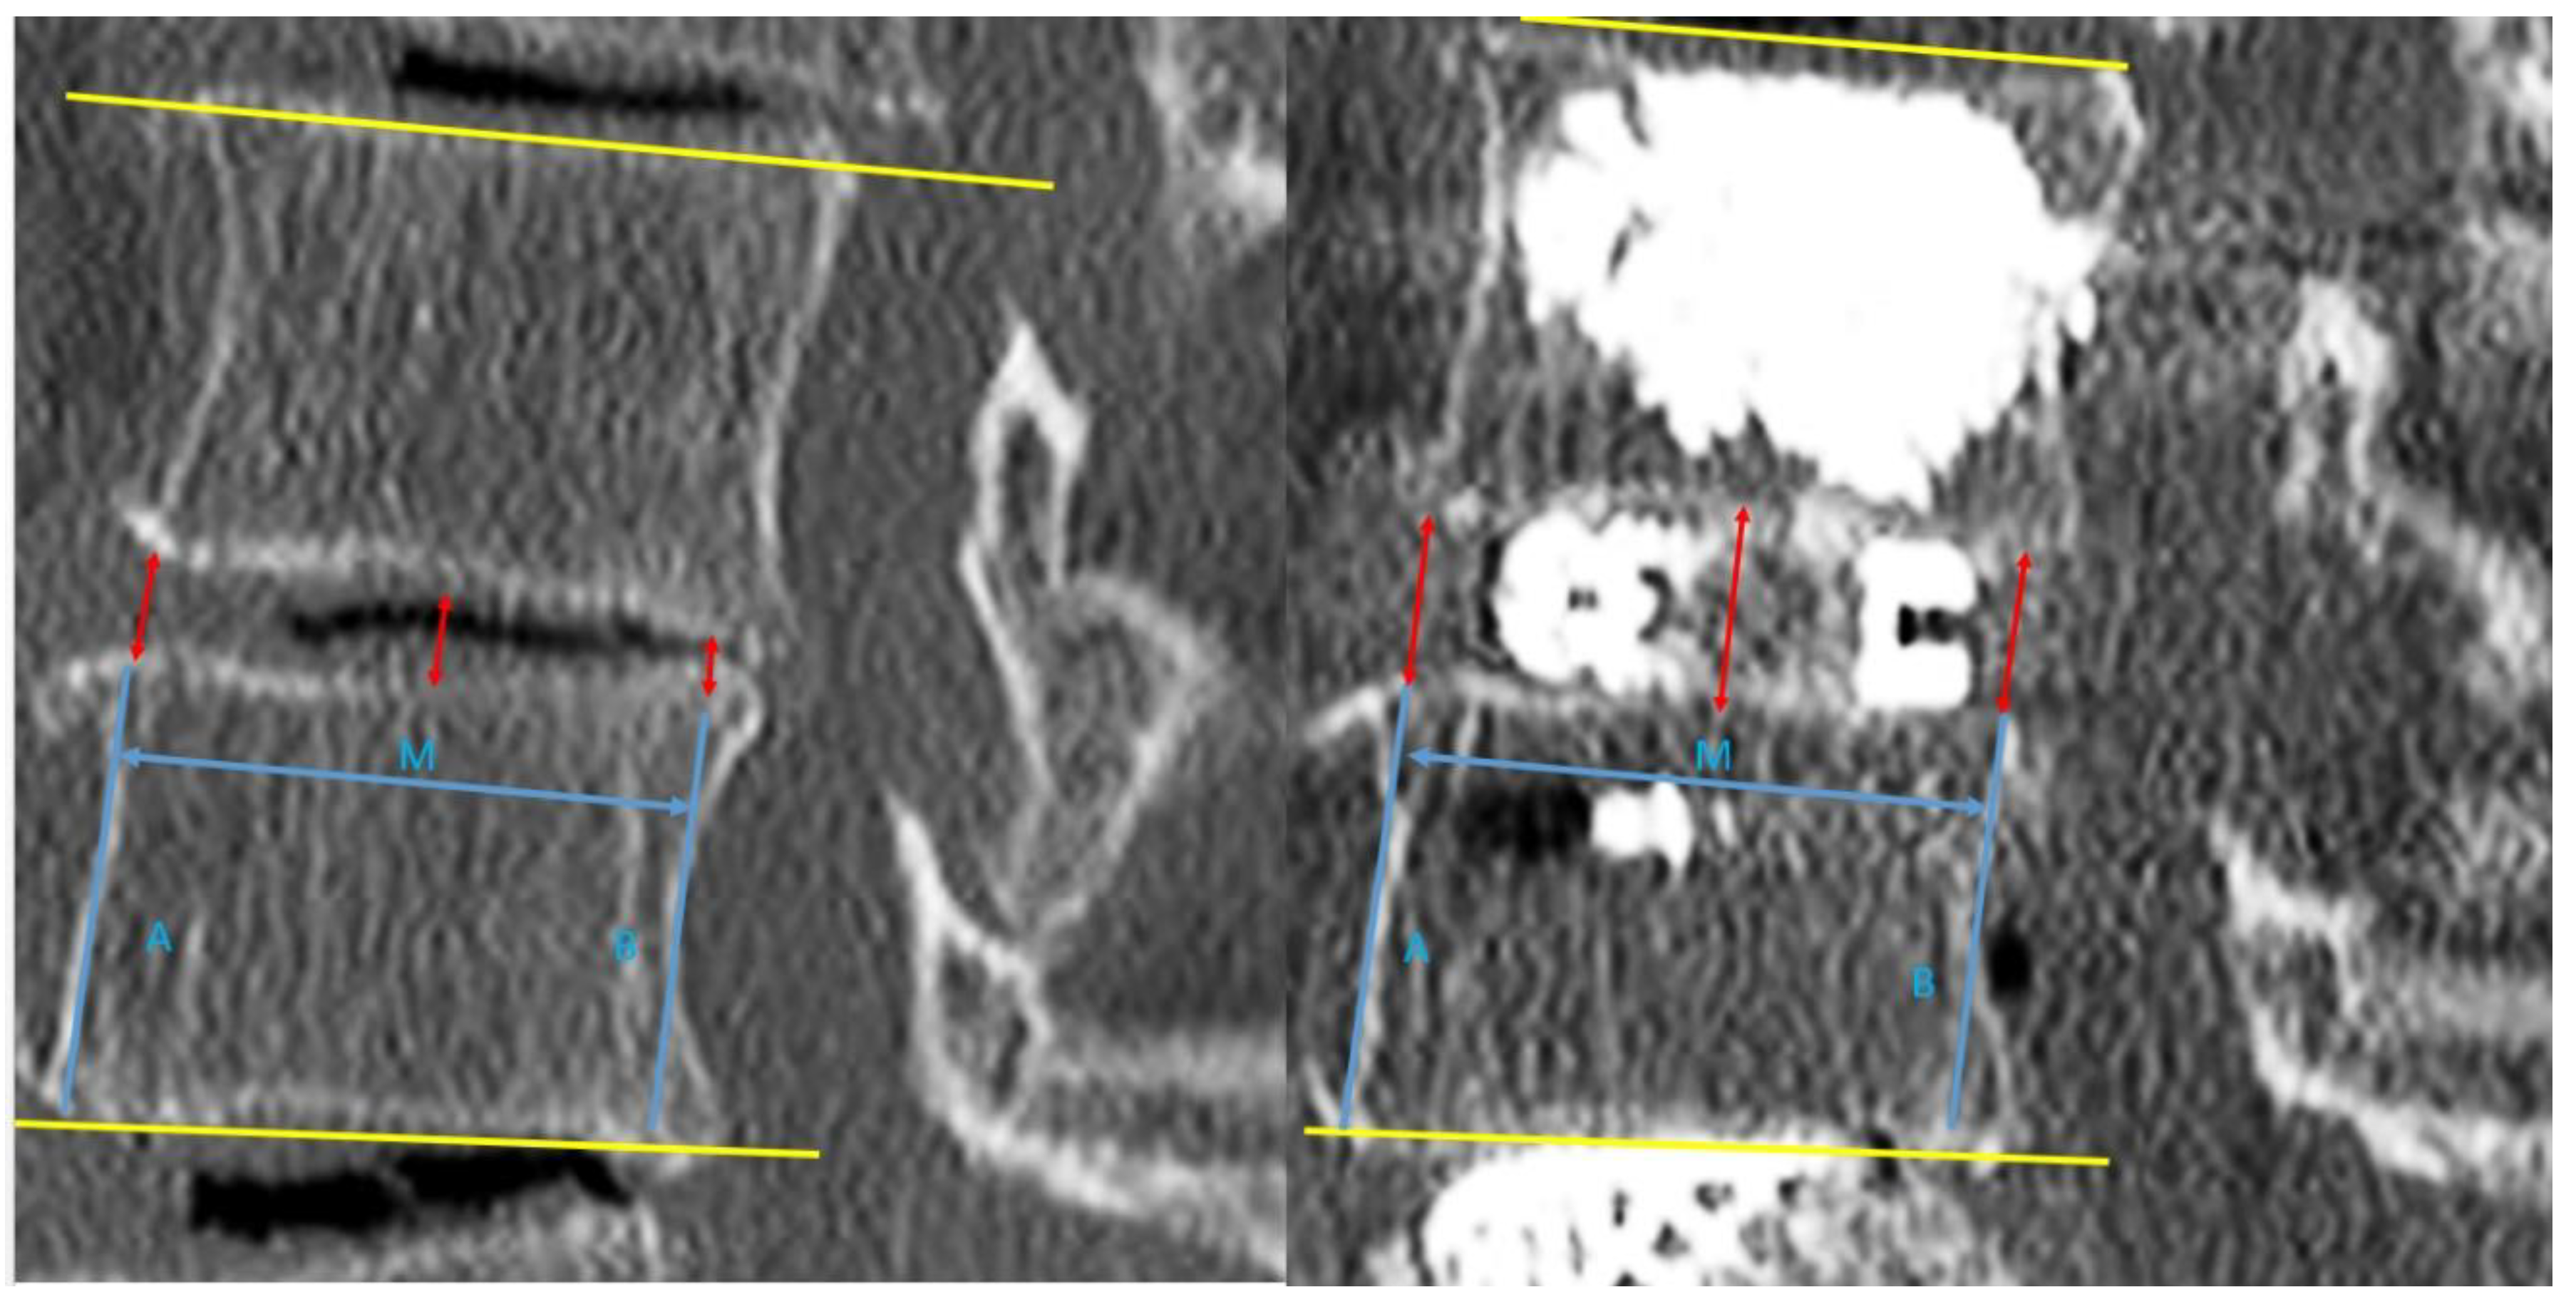

For post-operative evaluation in this cohort of patients, we evaluated clinical outcomes of Visual Analogue Scale at pre-operative, 1 week post-operative, 3 months post-operative and final follow up. Early and late perioperative complications were documented. For radiological evaluation, CT lumbar spine evaluation was done on pre-operative and post-operative day one. We evaluated mid sagittal CT lumbar spine to measure anterior, middle and posterior disc height and focal segmental angle (Figure 3). CT evaluation at mid coronal lumbar spine was done to measure mid coronal disc height and coronal wedge angle (Figure 4).

Figure 3. Mid sagittal cut of CT lumbar spine for measurement of parameters with left picture showed pre-operative cut and right picture showed post-operative cut of mid sagittal CT lumbar spine. Anterior vertebral line was drawn for caudal vertebra (line A) and anterior disc height was measured from the line parallel to line A from the caudal end plate to the cephalad end plate. The posterior vertebra line was drawn for caudal vertebra (line B) and posterior disc height is measured from line parallel to line A from caudal end plate to cephalad end plate. Middle disc height is measured at the end plate in the midpoint of lines A and B (M point) to the corresponding cephalad vertebral body end plate.

Brainsci 10 00373 g003